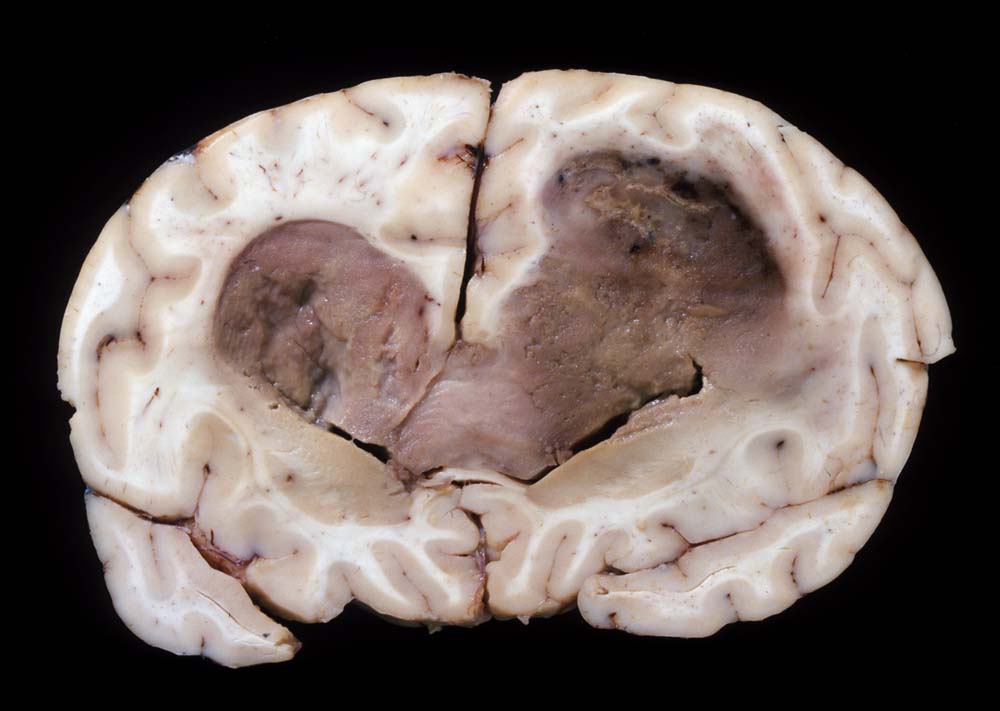

Bevorzugte Lokalisationen sind das Marklager des Frontal- und Temporallappens. Glioblastome des Hirnstammes sind selten und betreffen meist Kinder. Von dort breiten sie sich oft über den Balken schmetterlingsförmig auf die Gegenseite aus. Weniger als 5% der Tumoren wachsen multizentrisch. Eine Aussaat in den Subarachnoidalraum mit Metastasierung über den Liquor findet sich selten. Noch rarer sind hämatogene Metastasen in extraneurale Organe.

Morphologie:

Die Schnittfläche ist auffallend bunt. Dies ist bedingt durch ein Nebeneinander von graurotem vitalem Tumorgewebe, gelben Nekrosen, roten Einblutungen und gelegentlich grünlichen Gallertzysten.

Makroskopie